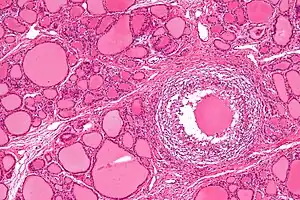

| Micrograph showing a granuloma in subacute thyroiditis. H&E stain. | |

De Quervain's thyroiditis, also known as subacute granulomatous thyroiditis or giant cell thyroiditis, is a member of the group of thyroiditis conditions known as resolving thyroiditis. People of all ages and genders may be affected.

Patients will experience a hyperthyroid period as the cellular lining of colloid spaces fails, allowing abundant colloid into the circulation, with neck pain and fever. Patients typically then become hypothyroid as the pituitary reduces TSH production and the inappropriately released colloid is depleted before resolving to euthyroid. The symptoms are those of hyperthyroidism and hypothyroidism. In addition, patients may suffer from painful dysphagia. There are multi-nucleated giant cells on histology. Thyroid antibodies can be present in some cases. The clinical presentation during the hyperthyroid phase can mimic those of Diffuse Toxic Goiter or Graves' disease. In such cases, a radionuclide thyroid uptake and scan can be helpful, since subacute thyroiditis will result in decreased isotope uptake, while Graves' disease will generally result in increased uptake. Distinguishing between these two types of disease is important, since Graves' disease and Diffuse Toxic Goiter can be treated with radioiodine therapy, but subacute thyroiditis is usually self-limited and is not treated with radioiodine.